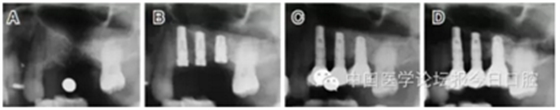

病例8 多顆種植體植入(圖10)

圖10